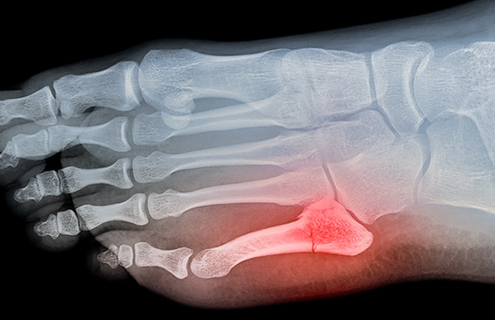

What you should know about a broken pinky toe